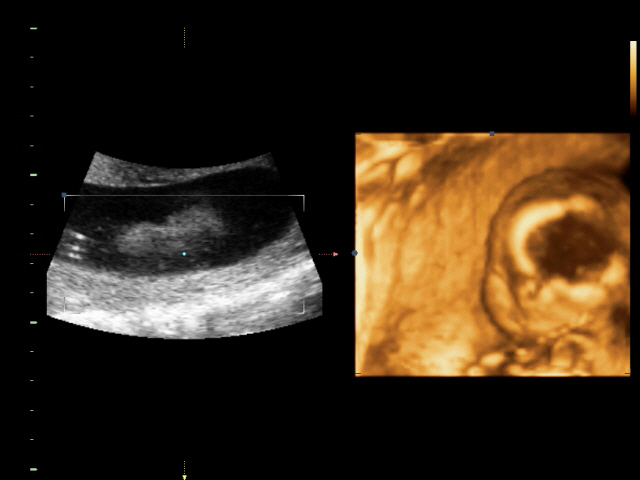

УЗИ, КТГ, доплерСходили всей семьей на 4D УЗИ! Определили нам пол окончательно и бесповоротно! Мальчик! Показали писюн! Так здорово! Я просто поверить не могу! А ведь он мне два раза снился! Настоящий реальный мужчина! Все показатели у нас в норме.